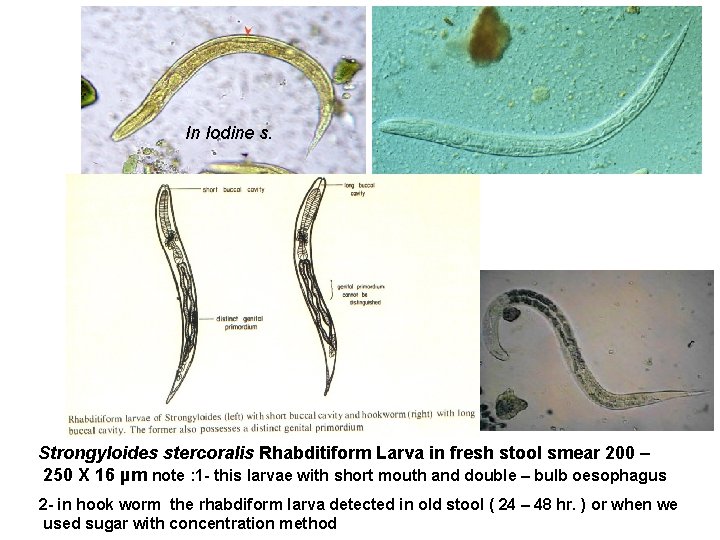

In Iodine s. Strongyloides stercoralis Rhabditiform Larva in fresh stool smear 200 – 250 X 16 µm note : 1 - this larvae with short mouth and double – bulb oesophagus 2 - in hook worm the rhabdiform larva detected in old stool ( 24 – 48 hr. ) or when we used sugar with concentration method